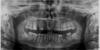

Mila07 Опубликовано 10 февраля, 2013 Поделиться Опубликовано 10 февраля, 2013 Уважаемые профессионалы, обращаюсь к Вам за помощью. Сделала ортопантомограмму, помогите понять, что это у меня на панорамном снимке: с правой стороны верхней челюсти над зубами светлое большое пятно (на снимке - слева). Может киста? Заранее благодарю всех ответивших. Ссылка на комментарий

Bier Опубликовано 10 февраля, 2013 Поделиться Опубликовано 10 февраля, 2013 Похоже на то, сделайте КТ Ссылка на комментарий

АнтонТЛТ Опубликовано 10 февраля, 2013 Поделиться Опубликовано 10 февраля, 2013 Скорее всего это киста от зуба, которая располагается в гайморовой пазухе. 2 Ссылка на комментарий

IvanK Опубликовано 11 февраля, 2013 Поделиться Опубликовано 11 февраля, 2013 о других каких именно? (на Ваш взгляд). Мне рекомендовали удалить верхние зубы мудрости, нижний слева (черный который на снимке справа, не знаю как он по нумерации) я уже удалила. Остальные , как мне сказали, в порядке...как-то так:Профессиональная гигиена + обучениеУдаление верхних и нижных 8-ок, слева внизу 6-каПротезирование верхней правой 5-еи - имплантация? Консультация ортопедаЛечение 6ки с кистой? Консультация терапевта Ссылка на комментарий